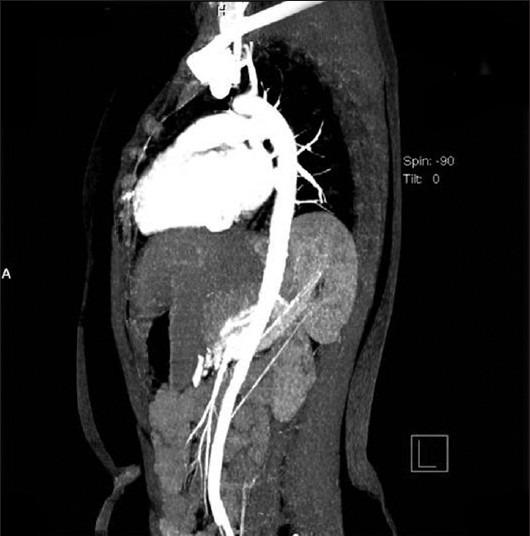

Bochdalek hernia is a congenital diaphragmatic defect that allows abdominal viscera to herniate into the thorax. Intrathoracic kidney is a very rare finding representing less than 5% of all renal ectopias. A 20 year old female presented with complaints of dry cough since 15 days and intermittent fever of 4 days duration. As part of routine investigation chest X-ray was done which showed a left retro-cardiac homogenous opacity, rest of the lung field appeared normal. Abdominal ultrasound showed the right kidney to be normal, left kidney was not visualized. Computed tomography scan demonstrated left-sided Bochdalek hernia with the left kidney within the thorax. An IVP was done to confirm the diagnosis. Many a times intrathoracic kidney is confused with a thoracic mass and the patient undergoes a battery of unnecessary investigations, surgical interventions and image guided biopsies for the same, hence to avoid this we are reporting this case.

博赫dalek疝是一种先天性膈缺陷,可使腹腔脏器疝入胸腔。胸腔内肾是一种非常罕见的发现,占所有肾异位的比例不到5%。一名20岁女性自15天前开始出现干咳,持续4天间歇性发热。作为常规检查的一部分,进行了胸部X线检查,显示左心后均匀性致密影,其余肺野正常。腹部超声显示右肾正常,左肾未显示。计算机断层扫描显示左侧博赫dalek疝,左肾位于胸腔内。进行了静脉肾盂造影以确诊。很多时候,胸腔内肾会与胸部肿块混淆,患者为此接受了一系列不必要的检查、手术干预和影像引导下活检,因此为避免这种情况,我们报告此病例。